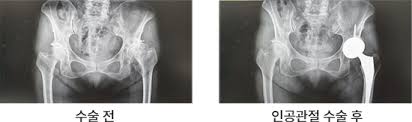

- 인공관절 치환술: 가장 일반적인 고관절 수술입니다. 퇴행성 관절염이나 심한 외상으로 인해 고관절이 손상된 경우, 인공 관절로 대체합니다. 이 수술은 대개 1-2시간 가량 소요되며, 회복이 길어질 수 있습니다.

각 수술 방식에 따라 환자의 상태를 고려한 특화된 치료 계획이 필요합니다. 예를 들어, 인공관절 치환술을 받을 경우에는 십여 주의 회복 기간 동안 물리 치료와 약물 치료가 반드시 포함되어야 합니다. 반면 관절경 수술의 경우에는 초기 회복 단계에서의 가벼운 운동과 체중 부하가 더 강조될 수 있습니다.